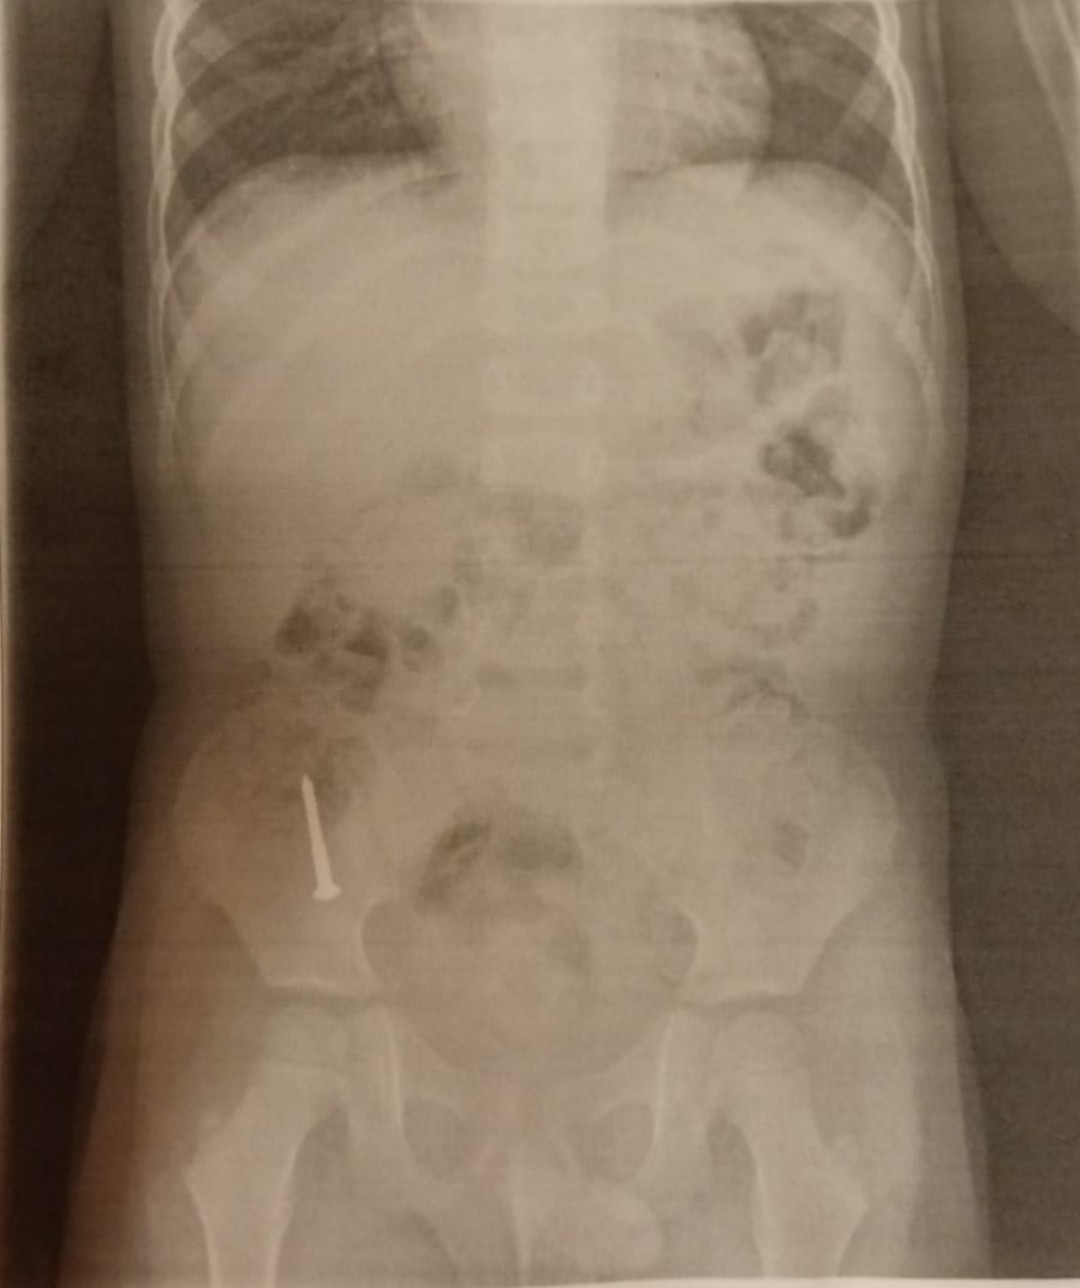

@anonym_autor ak mas podozrenie, ze zjedol klinec, tak smer pohotovost, tam urobia jeden rtg brucha a vyriesi to zahadu

@anonym_autor kovové veci sú RTG kontrastné,čiže ich dobre vidno na RTG, dupľom sa na to zameraju, pri vyšetrení, keď ste uviedli podozrenie, že to dieťa asi zjedlo. každopádne ja osobne by som išla ešte raz k lekárovi a poprosila o kontrolnú RTG snímku brucha dieťaťa, môže sa stať, že bol klinček zle viditeľný resp neviditeľný na predošlej snímke, napr ho prekrývala chrbtica....